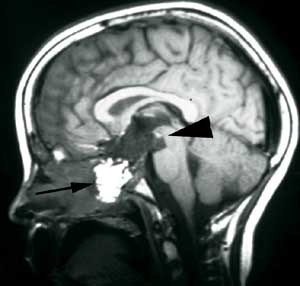

Pasienten ble henvist til Nevrokirurgisk avdeling, Rikshospitalet for vurdering med tanke på ytterligere kirurgi. Det forelå nå imidlertid en betydelig tumordestruksjon og invasjon i clivus av solide tumorkomponenter og ny cyste posterokaudalt mot 3. ventrikkel/hypothalamus og pons (fig 3a). Klinisk var pasienten også i meget rask forverring og hadde preoperativt redusert bevissthet, sløvet tale, ustø gange og urininkontinens.

Pasienten er ved tremånederskontroll betydelig restituert og har kun en mindre ekstremitetsparese. Som før den siste operasjonen er han blind og fullstendig hormonsubstituert. Postoperativ MR-undersøkelse viser ikke tegn til resttumor (fig 3b).